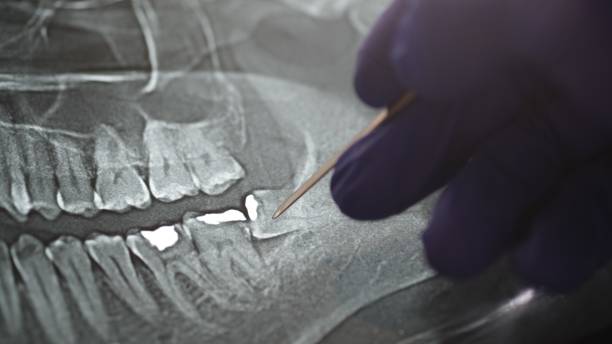

Some of the most common cases that require urgent dental visits include gingivitis, whose main symptoms are:

- Gum color changing to red along with visible swelling.

- Light bleeding during brushing.

- Persistent bad breath despite cleaning.

- Gum recession, or the feeling that teeth have suddenly elongated.

- Increased tooth sensitivity, especially when eating hot or cold foods.